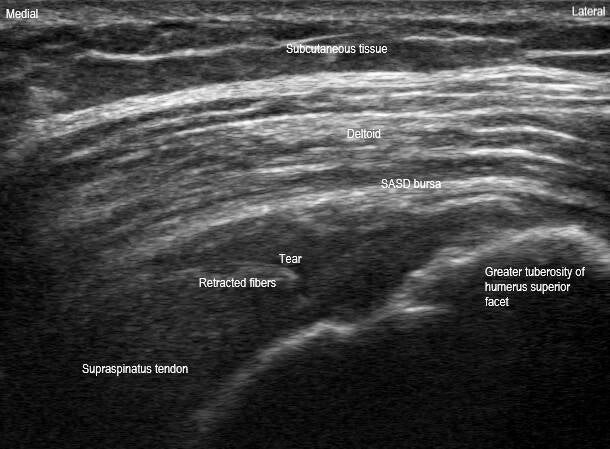

This is a long axis view in a anatomic oblique coronal plane and a short axis view in a anatomic oblique sagittal plane of the superior rotator cuff. These orthogonal views demonstrate an acute full thickness full width supraspinatus tendon tear. Retracted tendon stump fibers can be seen in the long axis view with a full thickness anechoic and hypoechoic defect and loss of fiber continuity. Dynamic maneuvers would show that the tendon does not move continuously together in long axis. The width and thickness of the tear can be appreciated on the short axis view. This is most likely acute given the findings of preserved superior convexity of the supraspinatus without dipping of the subacromial subdeltoid (SASD) bursa or synovial hypertrophy or infiltration. Additionally, acute tears may not show as much tendon retraction and should not have fatty infiltration or atrophy of the muscle belly. This particular patient fell on her shoulder approximately 2-3 weeks prior to this ultrasound scan.